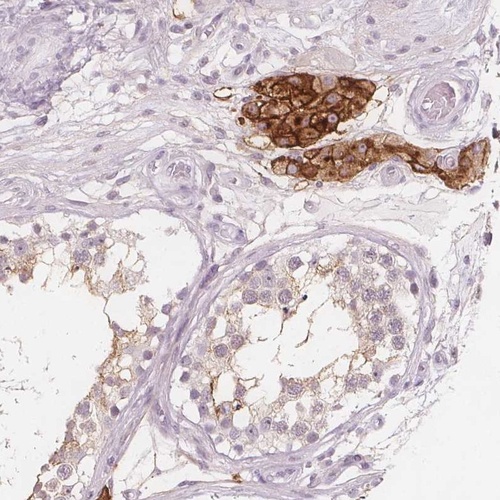

Immunohistochemical staining of human testis shows strong membranous positivity in Leydig cells.